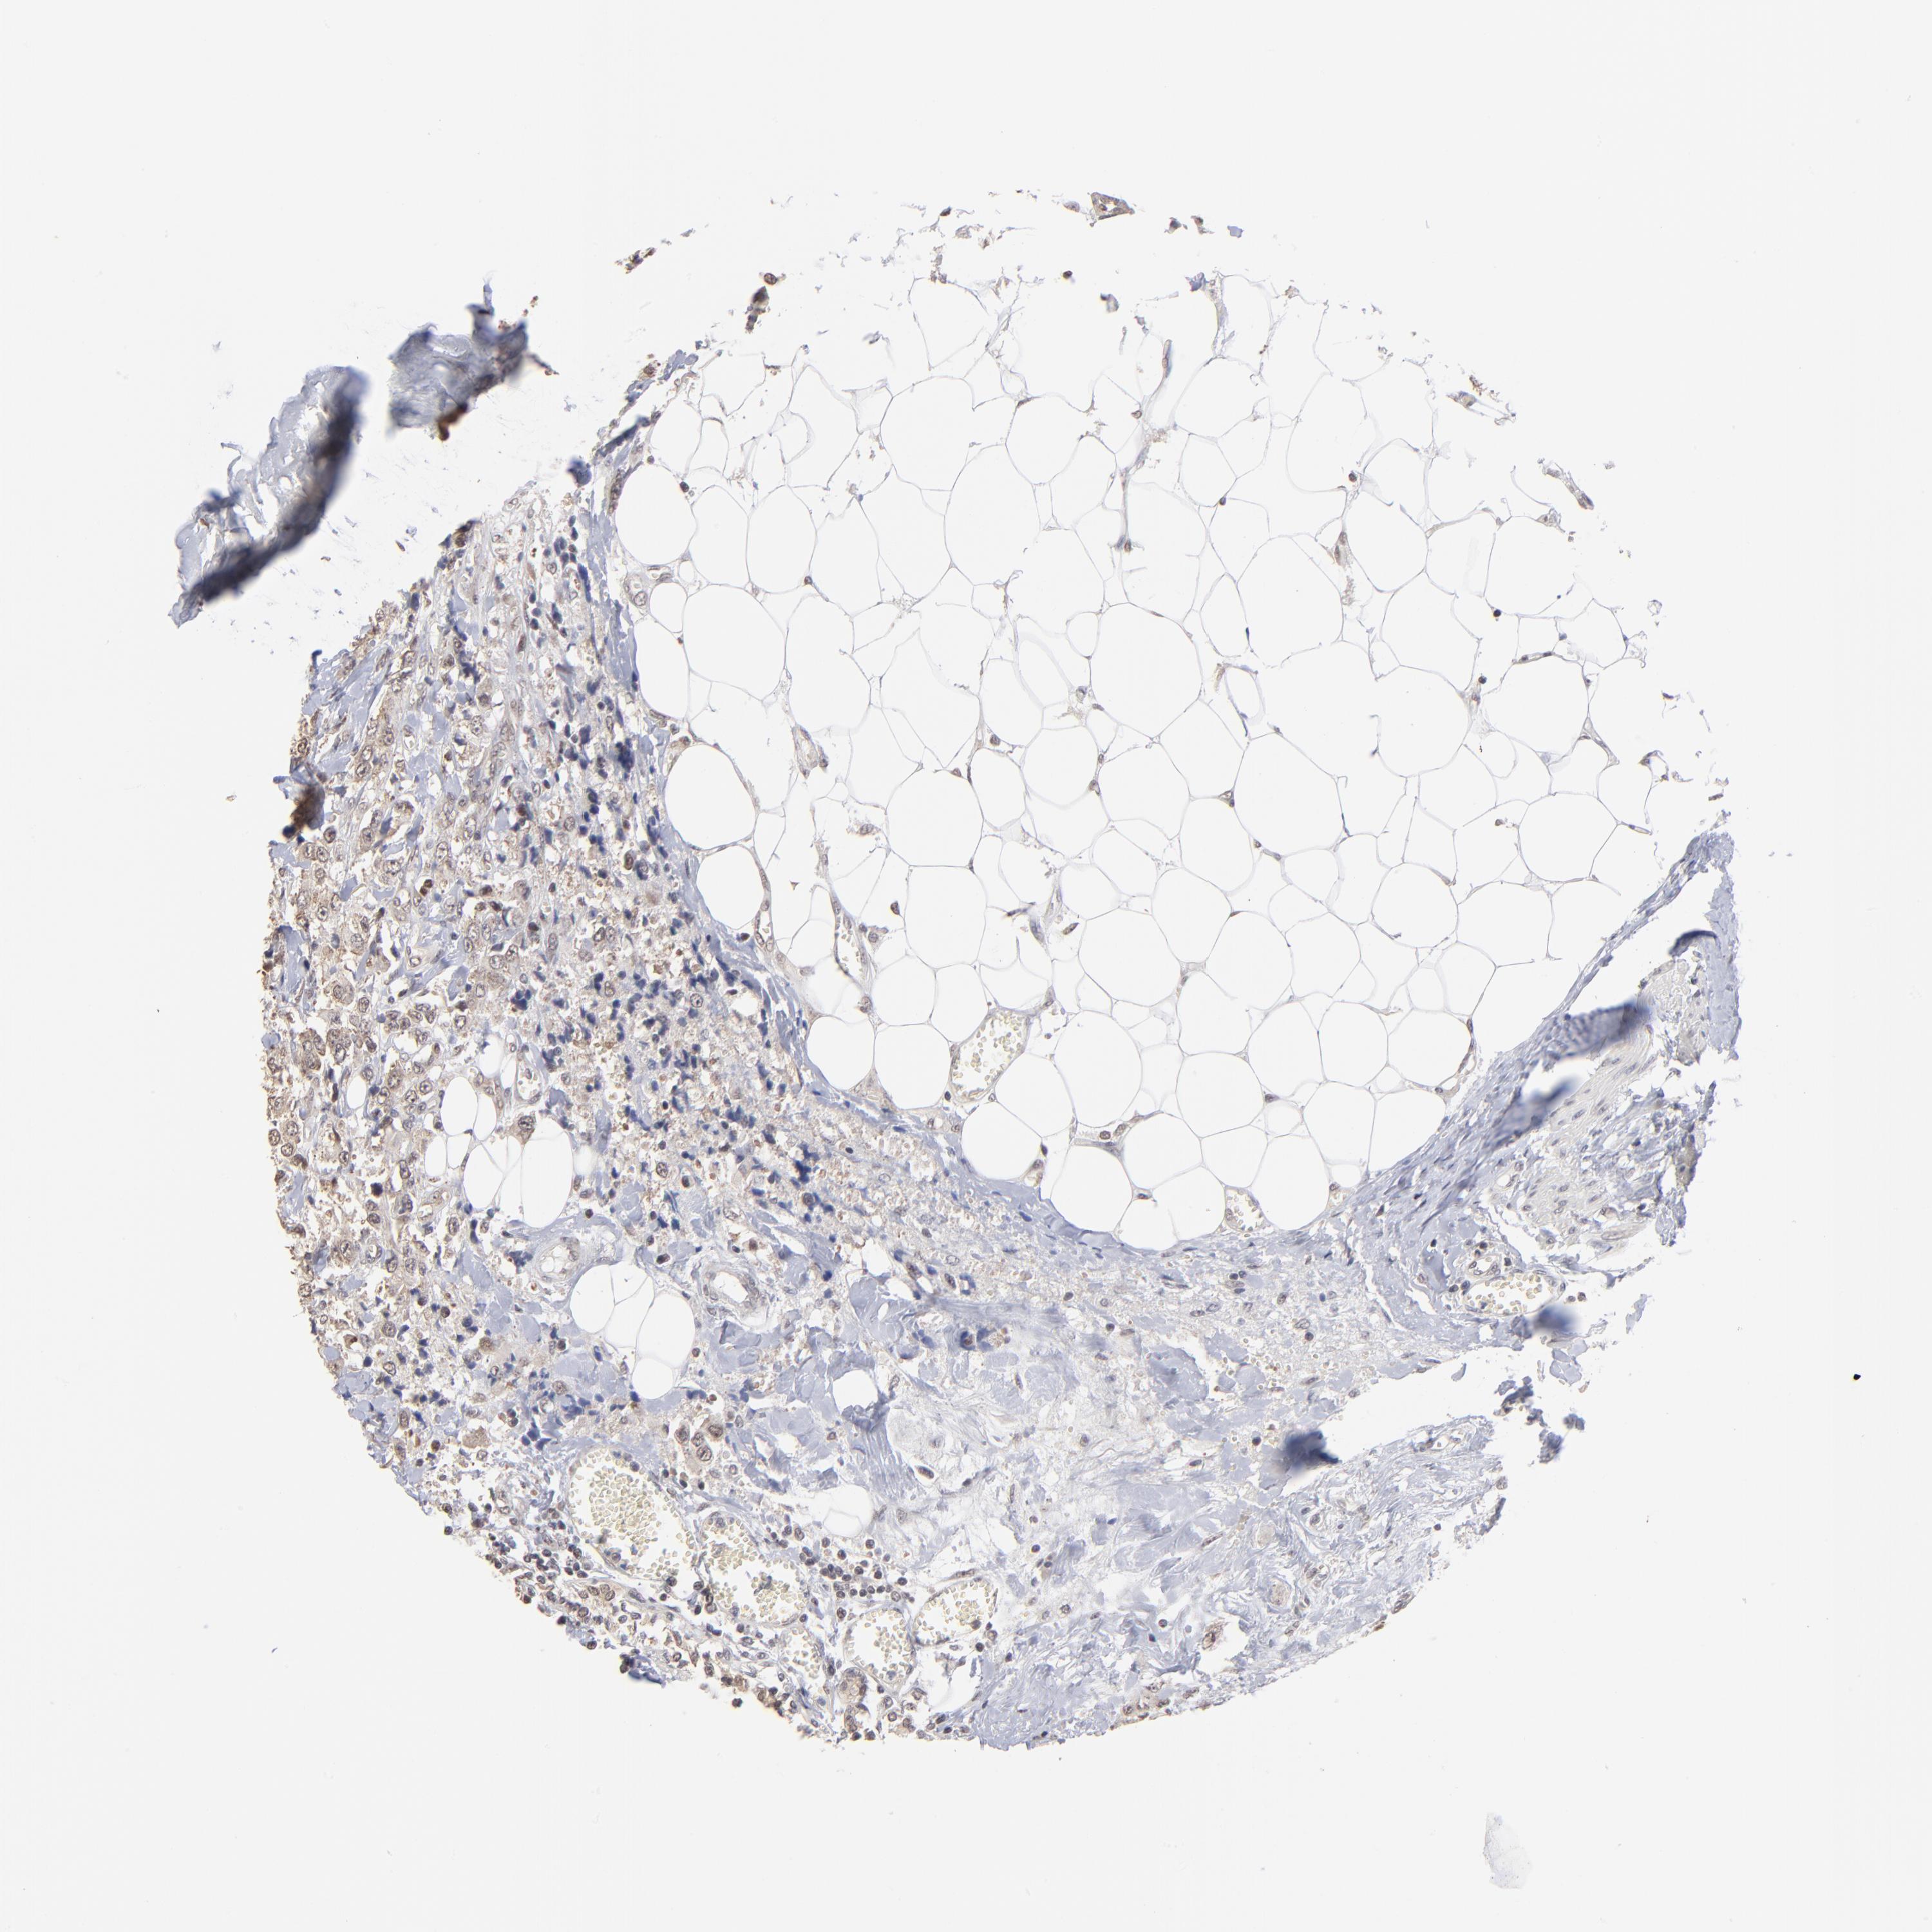

CANCER BREAST CANCER Show tissue menu

BRCA TCGA BRCA VALIDATION PROTEIN EXPRESSION

ANTIBODIES

AND

VALIDATION